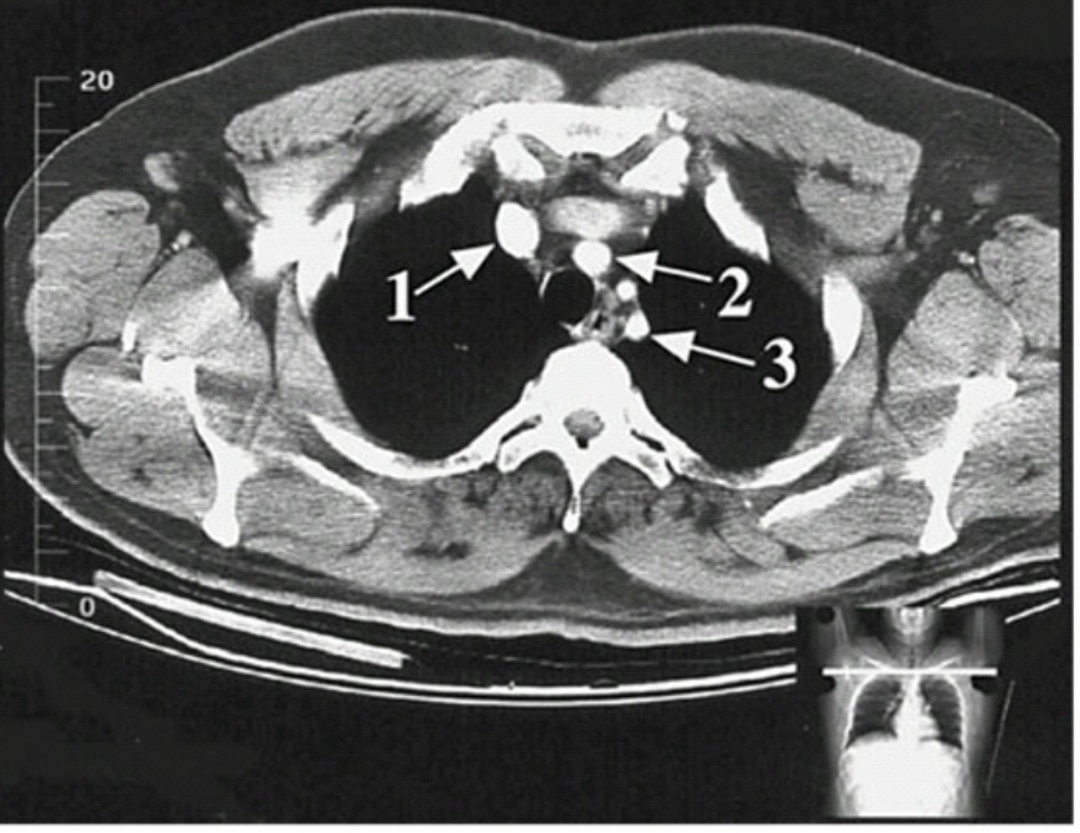

The structure indicated in arrow 1 is ????😊😊😊

a)brachiocephalic artery b)superior vencava c)lt common caratoid artery d)rt brachipcephalic vein e)none of these